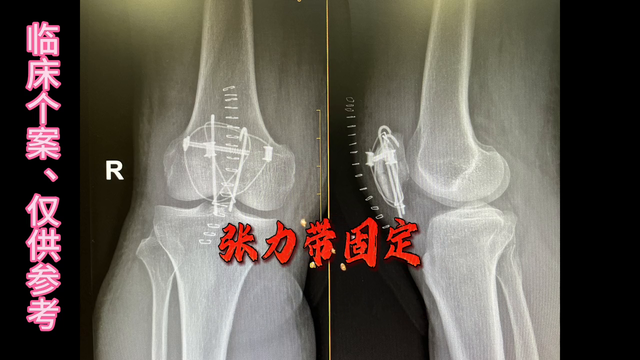

髌骨骨折是一种常见的疾病,许多人因地滑、滑倒或摔倒而膝盖跪地,导致髌骨开花。像这种移位髌骨,上下极分别被拉开,保守治疗效果不佳。手术可以恢复关节面的对位对线,让伸膝装置重新连续起来,这样膝盖才能恢复屈伸的功能。手术后也可以早期进行功能锻炼,降低膝关节僵硬的发生概率和程度。

一般来说,髌骨骨折需要进行张力带固定手术。张力带固定非常牢固,允许关节早期进行不负重的活动,且越活动固定得越紧。因此,髌骨骨折术后第二天即可开始下地活动和锻炼。